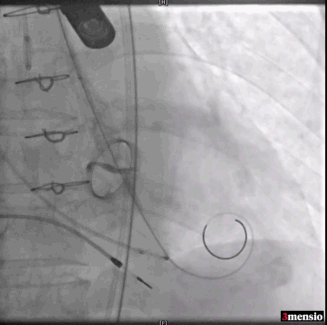

三叶瓣轻度钙化,右无可见钙化脊,瓣叶可见增厚,右冠高度可,左冠开口层面可见瓣叶,升主动脉未见明显扩张,法式窦及窦管交界稍小,两侧股动脉入路可,二尖瓣机械瓣置换术后。瓣环平均径23.7mm,LVOT26.8mm,STJ24.9mm,RCA18.4mm,LCA11.4mm。

2. STJ结构偏小且整体窦部结构不大,左冠瓣叶高度可达冠脉口,术中球囊预扩无造影剂下判断冠脉灌注情况难度大;

术中导丝跨瓣后20mm球囊预扩,超声判断冠脉风险尚可,植入L23 VenusA Plus可回收瓣膜位置良好,用23mm球囊后扩支架下缘,微少量瓣周漏。

术后即刻血压135/65mmHg,狭窄解除,释放后超声测量瓣下支架长度6mm标准位释放瓣膜位置完美。整台手术用时不足1.5小时,麻醉、超声等团队全程协作为手术顺利完成保驾护航。